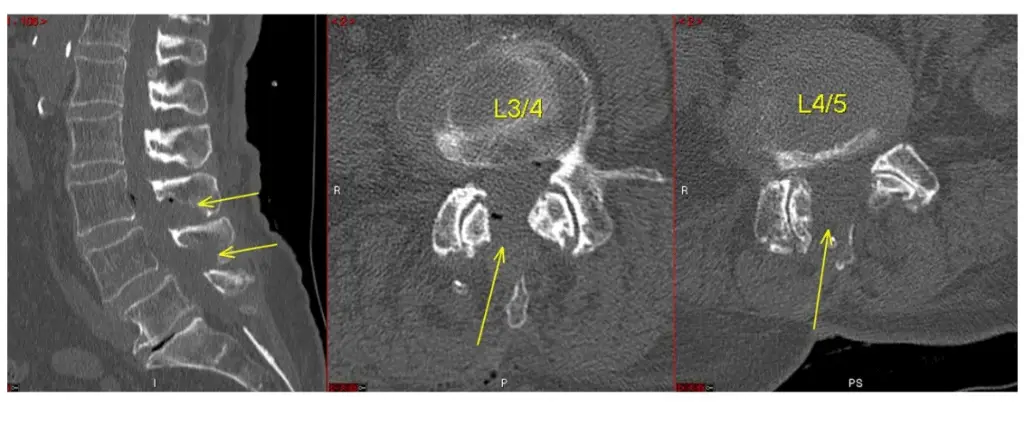

ULBD